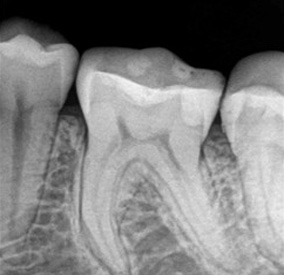

Zdjęcia punktowe (zębowe)

wykonuje się w celu diagnostyki jednego lub kilku sąsiadujących ze sobą zębów (1-4 zębów) kiedy pacjent zgłasza się do gabinetu z bólem zęba, w trakcie leczenia kanałowego czy podczas zabiegu implantacji.

Zdjęcia są również wykorzystywane do oceny tkanek w okolicy wierzchołków korzeni zęba.